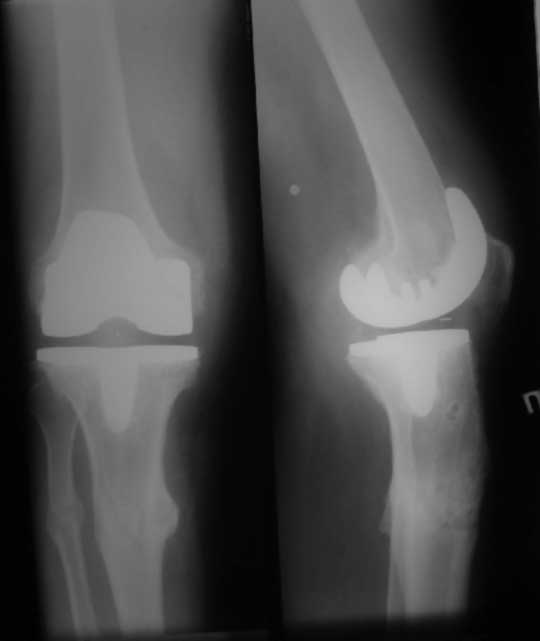

У пациента 50 лет имеется разгибательная контрактура через 8 меспосле ТКА. Уважаемые коллеги. Пациент 8 мес после операции ТКА, в анамнезе – неправильно сросшийся перелом голени, коррекция оси (снимки прилагаются. В настоящее время имеется разгибательная контрактура 10/5/0, на операционном столе было 90/0/5, на момент выписки движения 50/0/0 в надежде на дальнейшую разработку. До эндопротезирования 40/10/0. Глубокая инфекция исключена. Ротация бедренного компонента в норме (по КТ). Вопросы: насколько для такого ограничения критична некорректная установка б/б компонента (я намерял 7 град)? Причина нынешнего состояния, артрофиброз? Какие действия следует предпринять, удаление рубцов, релиз головок 4-главой мышцы? Что-либо другое, ваше мнение? С уважением, Максим Агалаков, Екатеринбург.

Рентгеновский снимок хороший, операция выполнена достойно, надколенник не смущает. Остаюсь на своем мнении, артролиз, если смущает давление надколенника при артроскопии помимо артролиза верхнего заворота, боковых каналов и переднего отдела, дополните латеральным релизом надколенника, чтоб уменьшить натяжение.